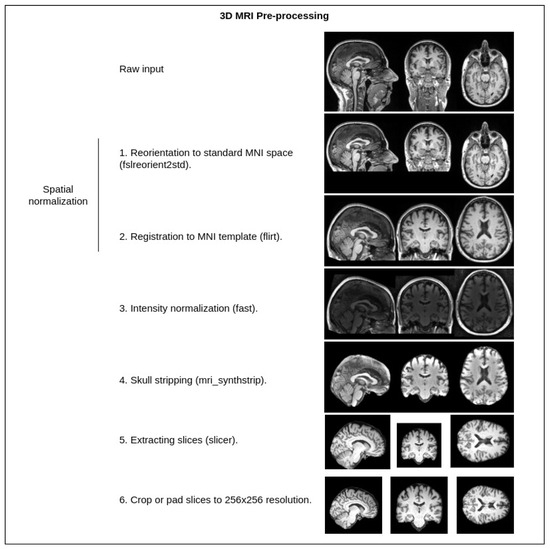

3. Materials and Methods

4.1. Experimentation Data

4.2. Implementation Details